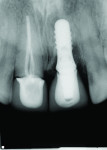

A 46-year-old woman presented with peri-implantitis surrounding tooth No. 9 and root resorption in tooth No. 8 (Figure 1). The crown restorations for both teeth demonstrated an improper fit along the gingival margins (Figure 2). In particular, the soft tissue at tooth No. 9 was inflamed as a result of poor implant abutment selection that placed the margin too deep within the tissue, which is contraindicated for cement-retained implant restorations. As noted previously, many causes of peri-implantitis are iatrogenic in nature,6 and cement-retained implant restorations require abutment placement at the correct margin level and precise removal of excess cement, to prevent development of inflammation.

A treatment plan was developed by Belkis del Puerto, DMD, and John Paul Gallardo, DDS, PA, to first address the peri-implantitis infection at tooth No. 9 and stabilize the already completely osseointegrated implant (Figure 3). Then, the soft tissue would be regenerated and recontoured (Figure 4). The clinical and laboratory protocol for creating the custom hybrid titanium and lithium disilicate abutments were dictated by the implant (eg, Straumann Tissue Level, Straumann, straumann.us) and materials (eg, IPS e.max®, Ivoclar Vivadent, ivoclarvivadent.com) used in this case.